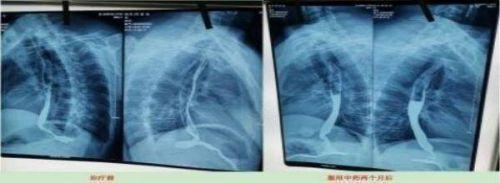

案例5、食道癌两个月清零

Case 5. Oesophageal cancer was cleared for two months

患者:刘喜良 男 46岁 食道中段癌

2023年10月9日CT影响报告诊断查出食管壁增厚,管腔狭窄,食管癌。找到陈海林老师使用中医药两个月治疗后CT显示食管各段顺利通过,食管恶性肿瘤治疗后改变。

Patient: Liu Xiliang, male, 46-year-old middle-esophageal cancer On 9 October 2023, CT affected the diagnosis of food tube wall thickening, lumen stenosis, and esophageal cancer. After finding Chen Hailin for two months, CT treatment showed the smooth passage of all section of the esophagus, and the esophagus of malignant tumor changed after treatment.

上图是服用两个月中药的前后对比图

Above is a comparison of before and after taking traditional Chinese medicine for two months

上图是服用两个月中药后检查报告对比图